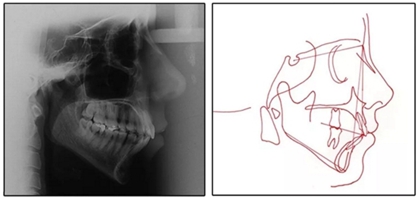

患者是一名39歲的白人婦女,病史不明。她主訴是她的右側(cè)顳下關(guān)節(jié)有不適癥狀,并希望改善她的笑容。她有一個對稱的臉型和一個II類2分類的微笑。她的側(cè)貌是凸的,90°的鼻唇角和骨性下頜骨發(fā)育不足??趦?nèi),上頜中線與面部重合,但下頜中線向右側(cè)偏移5mm;存在6mm的深覆蓋。她的兩側(cè)都是I類磨牙關(guān)系,左側(cè)是I類尖牙關(guān)系,右側(cè)是完全的II類尖牙關(guān)系。下頜右側(cè)第二前磨牙先天性缺失(圖1和圖2)。最初的全景片顯示了足夠的骨質(zhì)水平和全部的第三磨牙(圖3)。治療前的頭影測量片片和相應(yīng)的頭影測量圖(圖3)證實ANB為7°,Wits評估為6 mm的骨性II類錯合(表)。上頜切牙相對與面部和顱底的位置很好。下頜切牙前傾。診斷為II類2分類錯合畸形,伴有骨性下頜發(fā)育不足,右側(cè)顳下頜關(guān)節(jié)癥狀,下頜中線向右側(cè)偏移5mm,先天性右下第二前磨牙缺失。

圖3. 治療前頭影側(cè)位片,頭影測量描跡圖和全口X光片